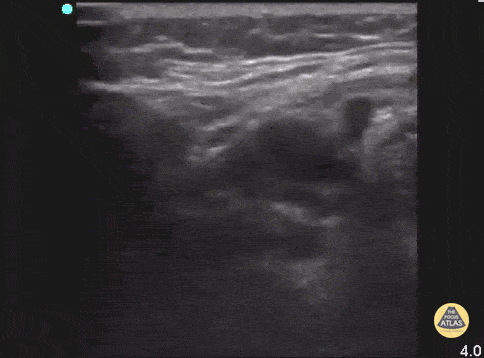

Soft Tissue - Sialadenitis (Postoperative)

55 y/o F with recent shoulder surgery 4 days prior, with three days of dysphagia and swelling under R jaw. POCUS reveals swollen submandibular gland with multiple hypoechoic areas, similar to cobblestoning, scattered through normal glandular tissue. CT demonstrated inflammation of submandibular gland and surrounding platysma with prominent ducts and an obstructing stone. Drs. Surriya Ahmad and John F Kilpatrick - Kings County/SUNY Downstate Emergency Medicine